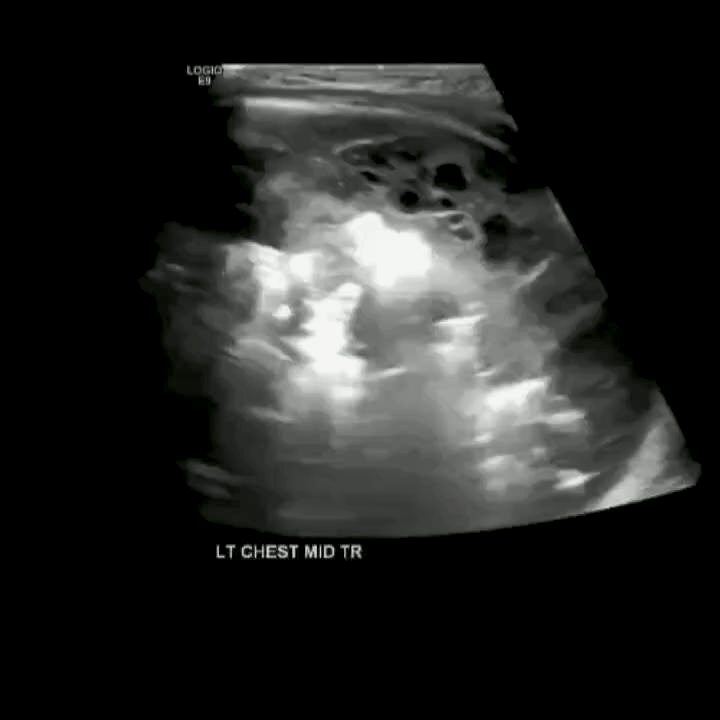

Consolidation

Hepatization of the lung parenchyma due to infiltration with fluid. May also have “air-bronchograms”.

Color doppler will show blood flow through the pulmonary vasculature.

In alveolar consolidation the lung parenchyma takes on the appearance of liver echotexture, “hepatization”. There may be air bronchograms present in consolidated tissue which appears as hyperechoic air bubbles with reverberation artifacts. Color doppler will show blood flow through the pulmonary vasculature.